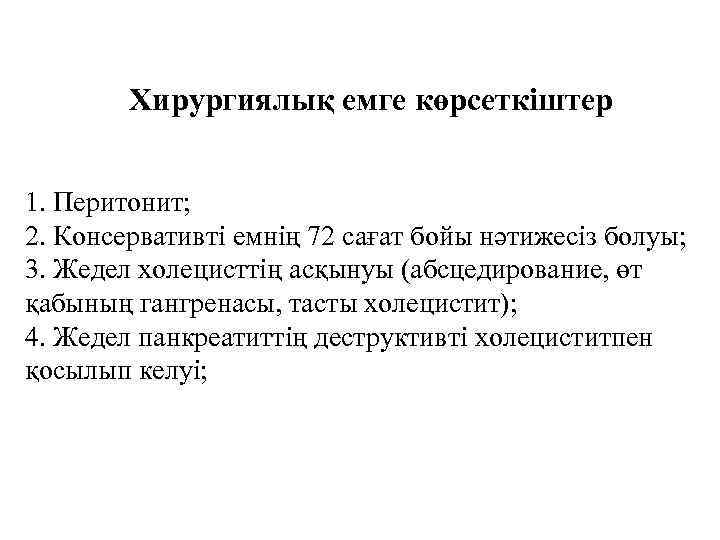

Хирургиялық емге көрсеткіштер 1. Перитонит; 2. Консервативті емнің 72 сағат бойы нәтижесіз болуы; 3. Жедел холецисттің асқынуы (абсцедирование, өт қабының гангренасы, тасты холецистит); 4. Жедел панкреатиттің деструктивті холециститпен қосылып келуі;